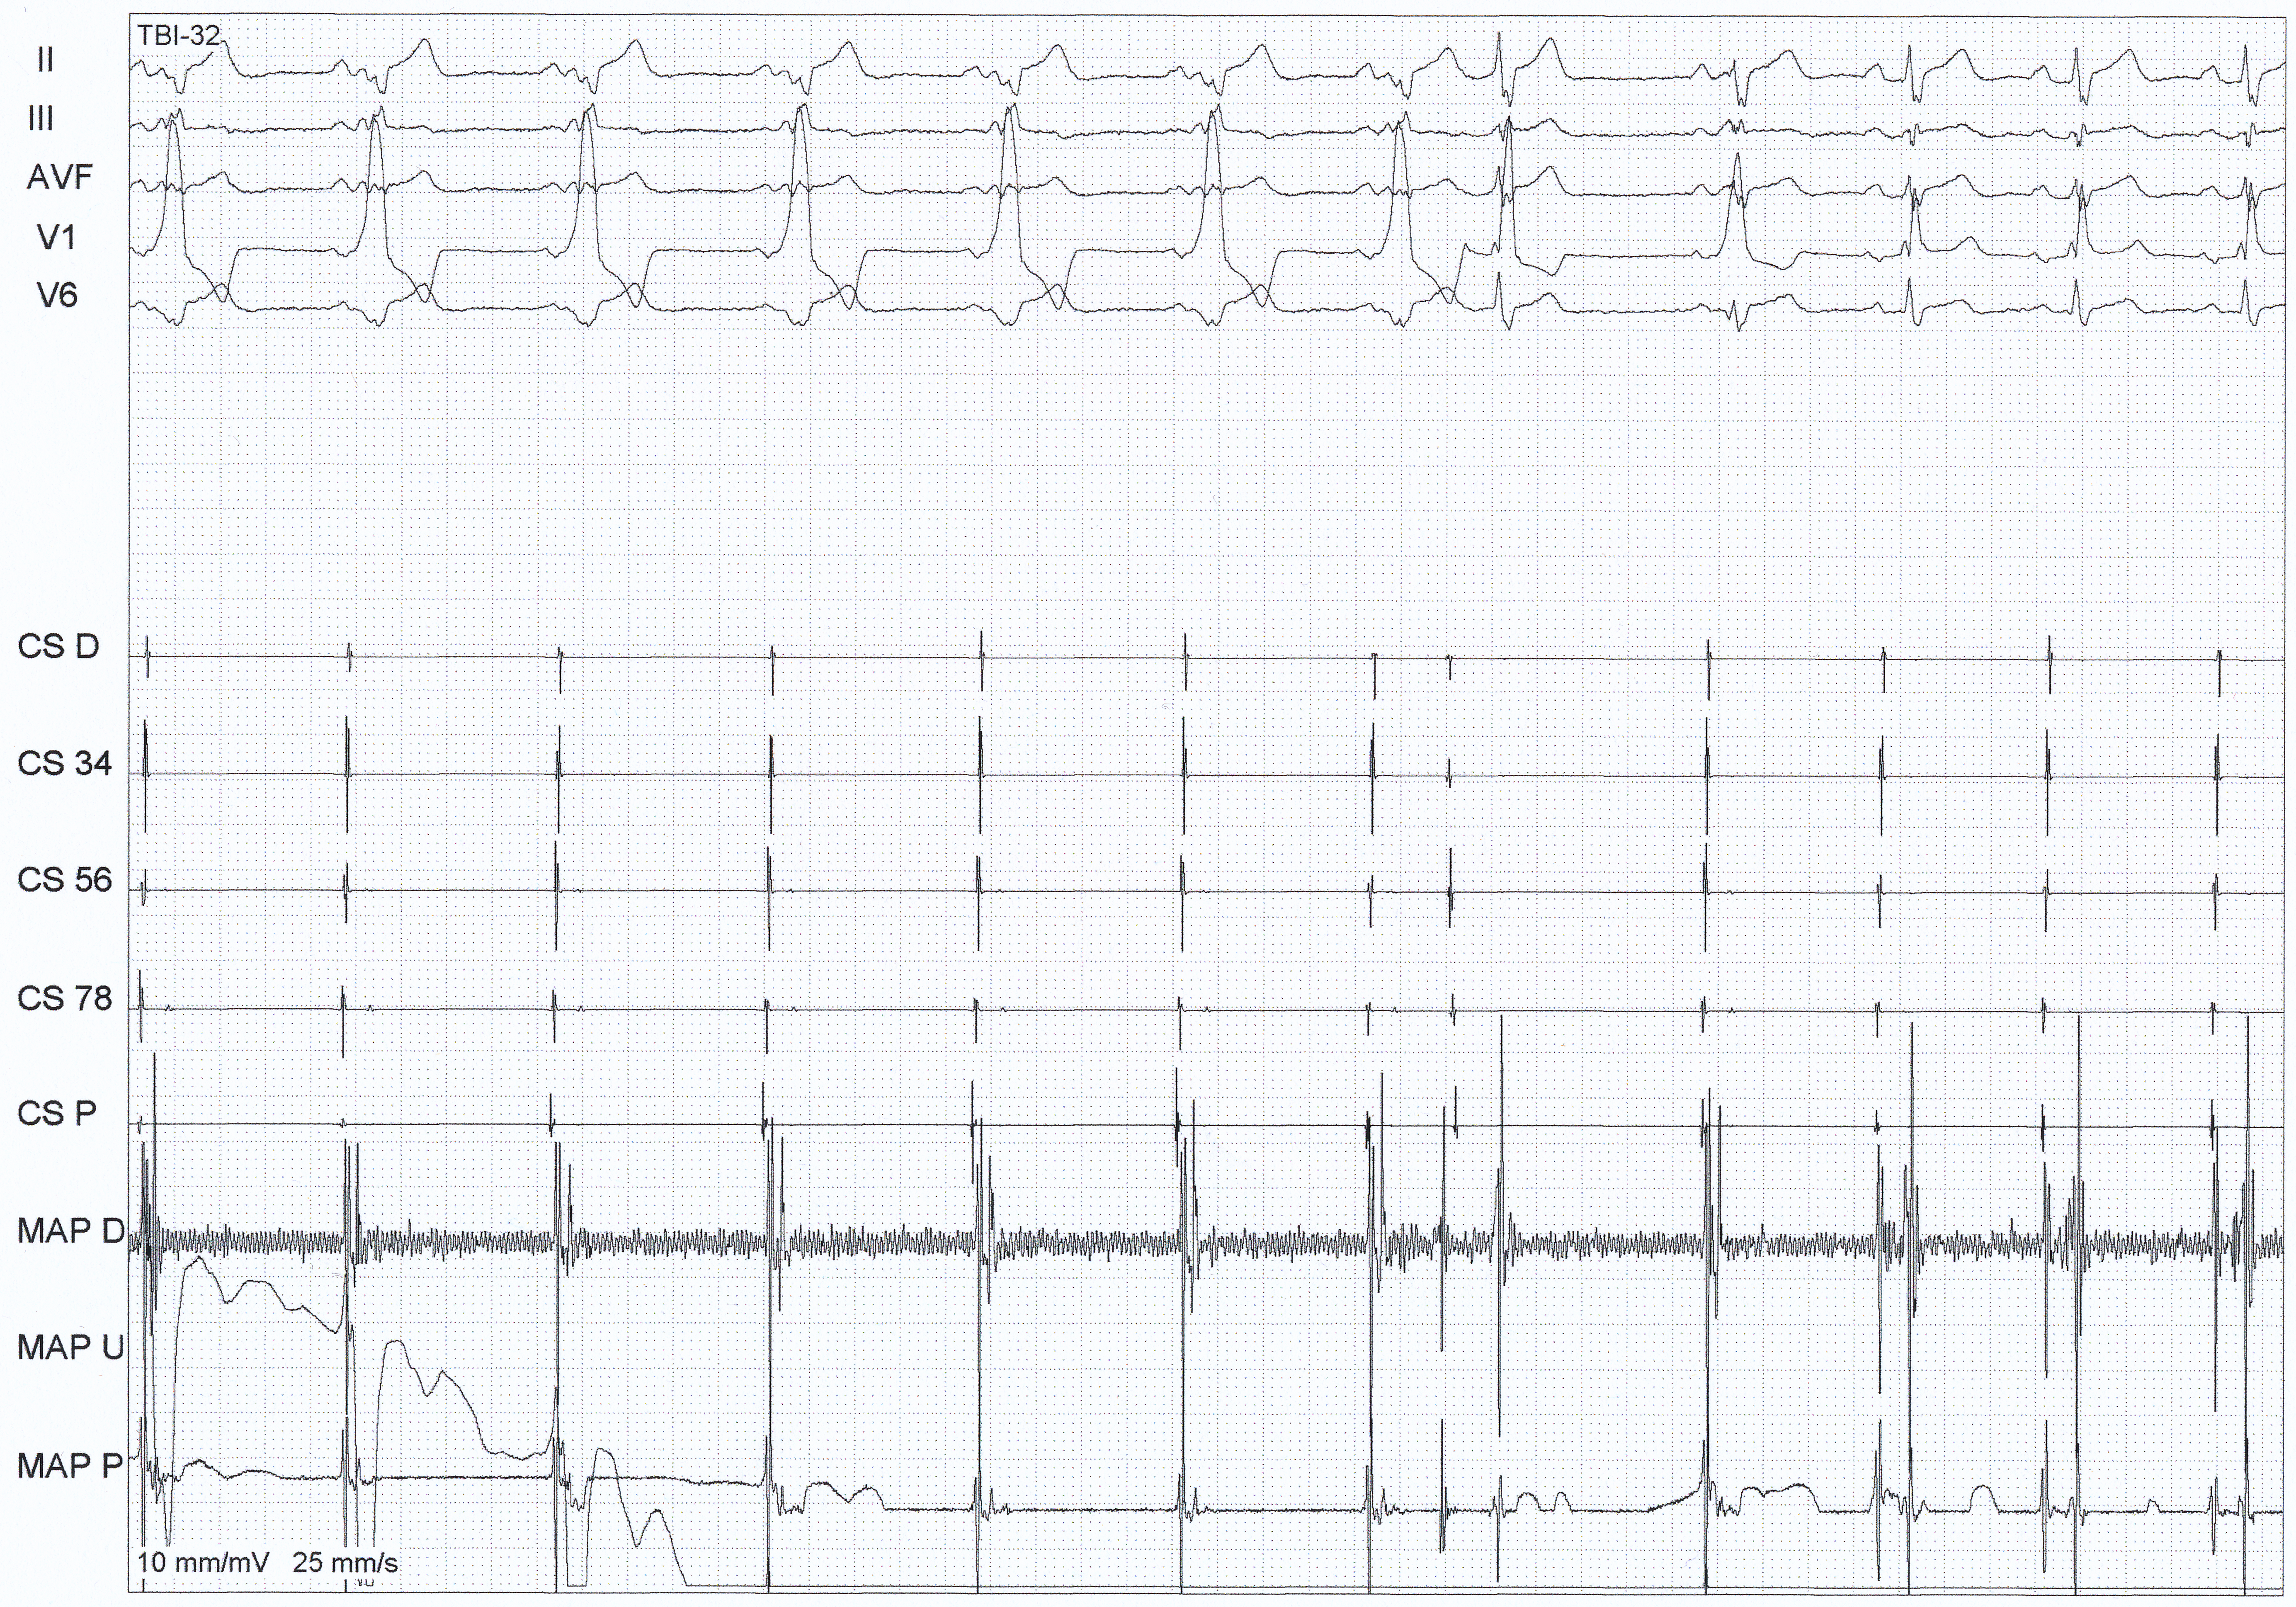

La phase initiale du projet fut riche en enseignements. La première session EP + ablation EP se déroula du 20 au 24 septembre 2015 par Dr. Marc Zimmermann et Mr Lionel Agnoletti

Finalement, il fut necessaire de créer une liste de candidats potentiels à l’ablation. Ablation pour AVRT, AVNRT, AT, FL, RVOT (pas pour FA, FL ou AT gauches et TV ischémiques)